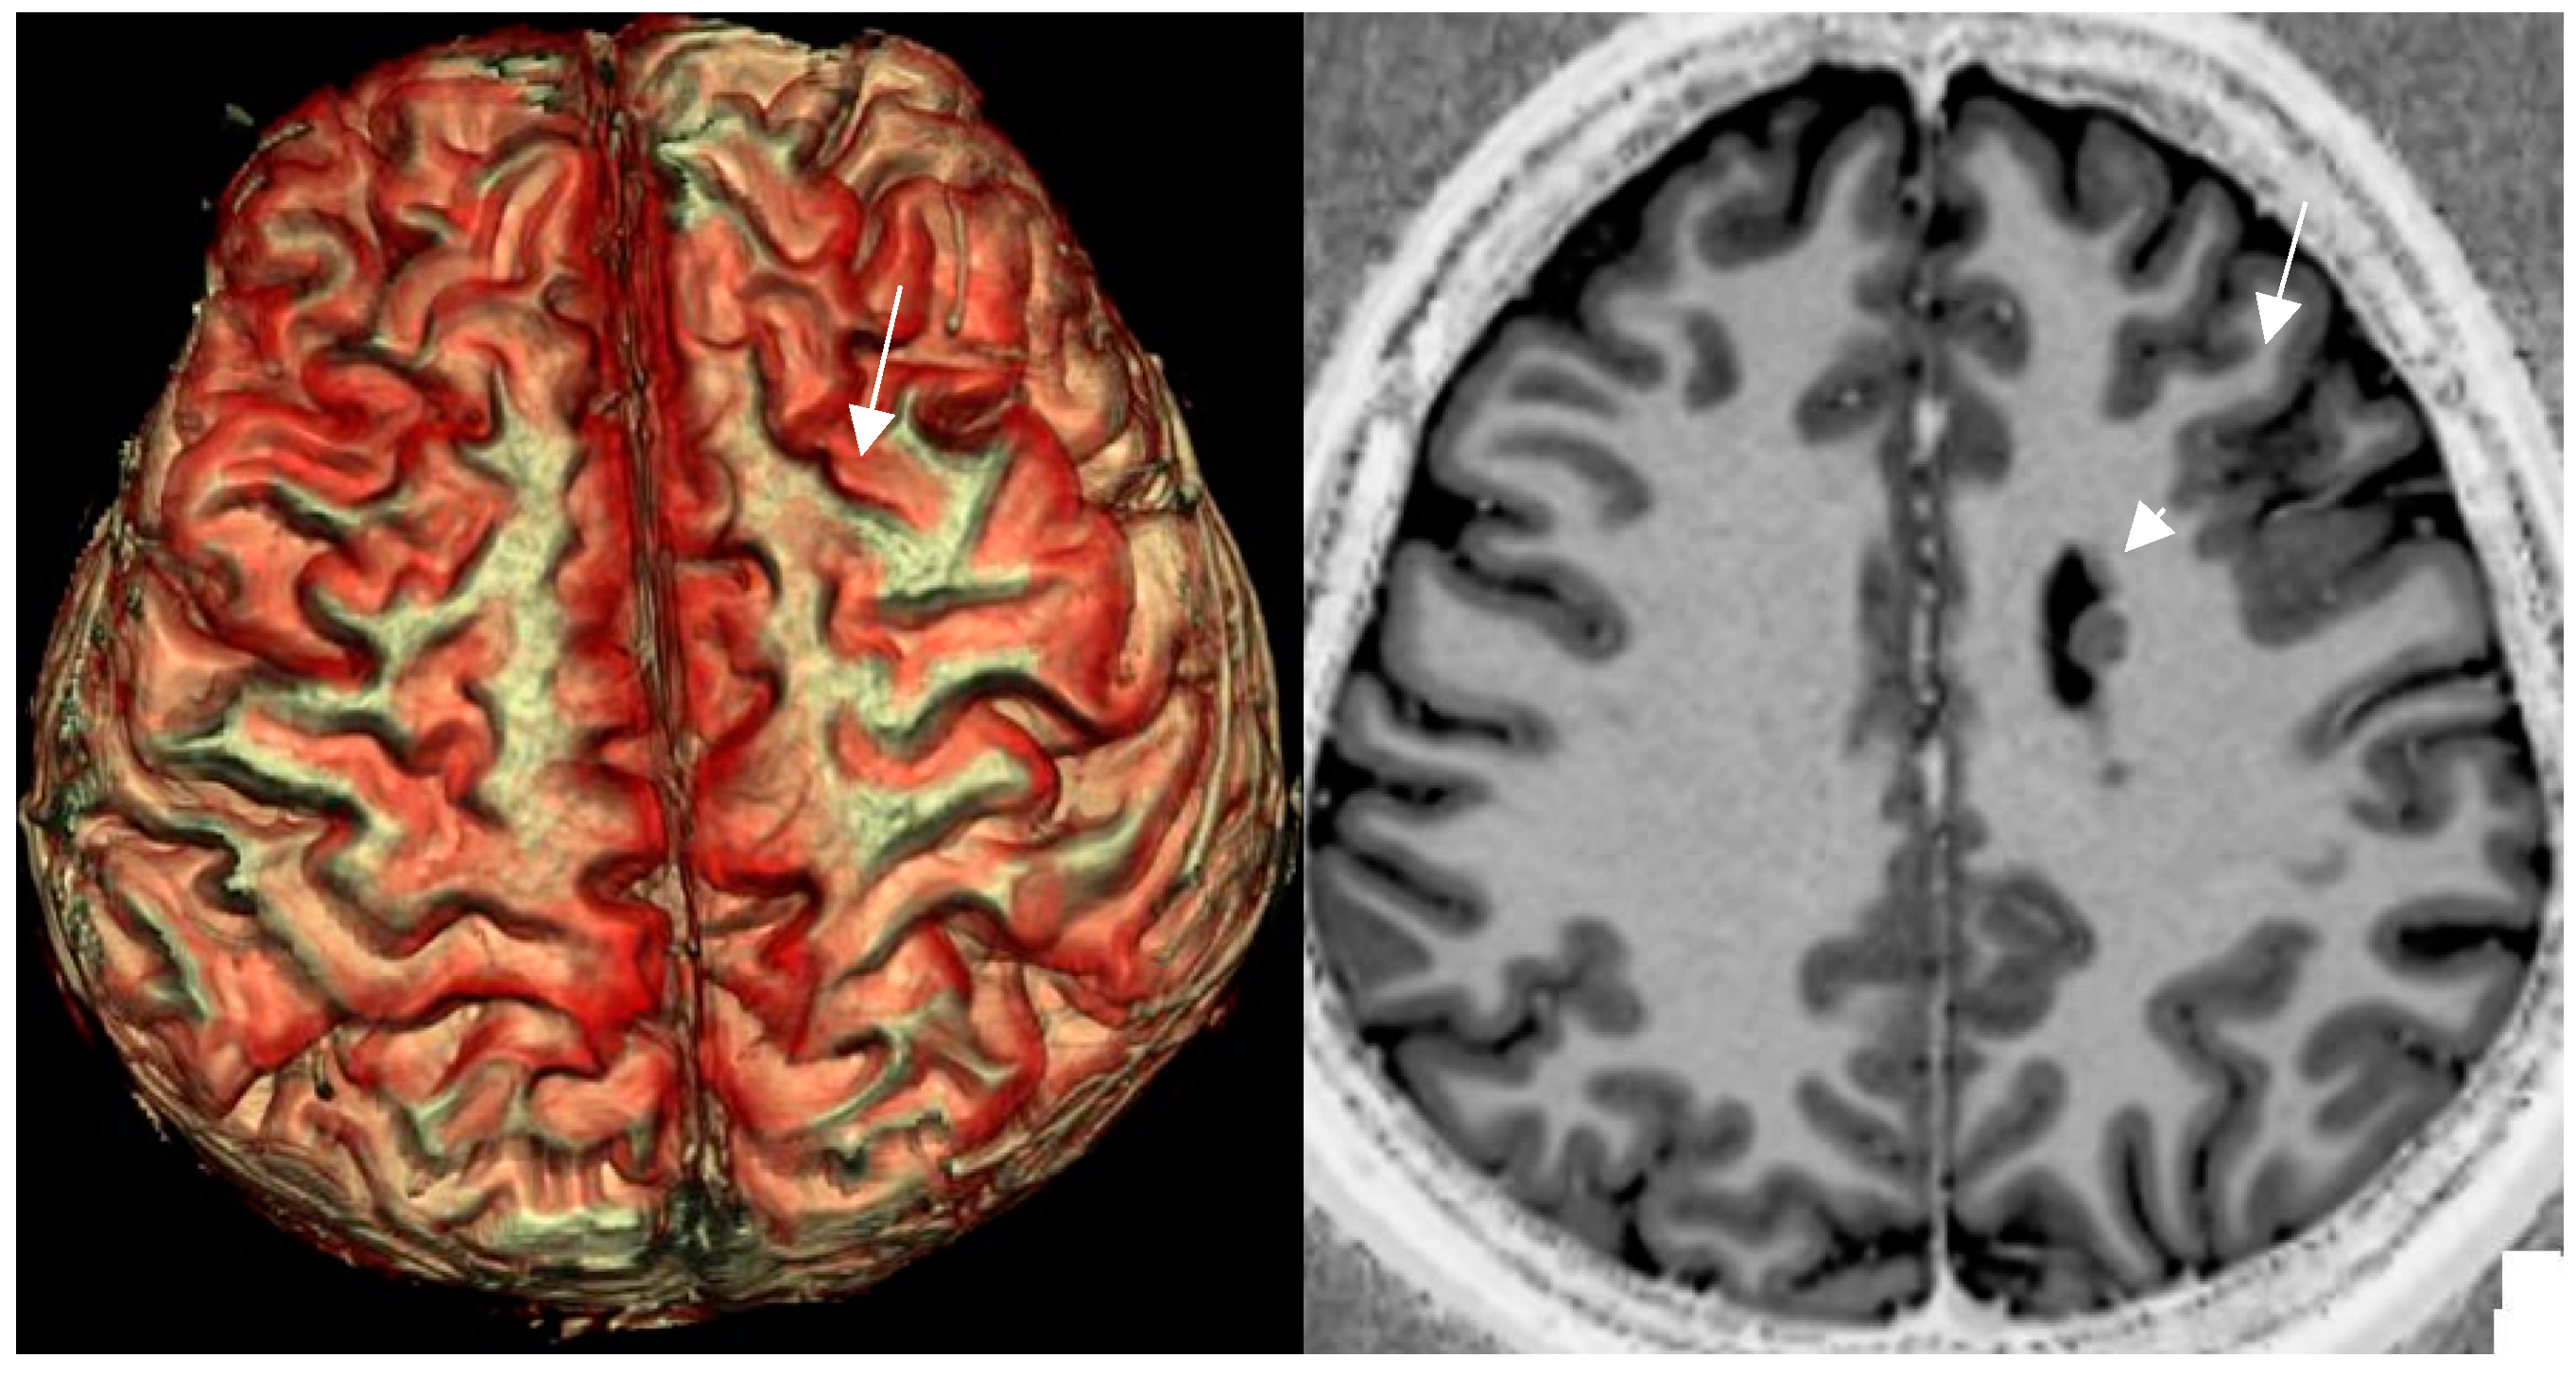

4.9. MR Fingerprinting Exploits Tissue Properties to Reflect “Activity“ of a Lesion

- Mellerio C,Roca P, Chassoux F, Daniere F, Cachia A, Lion St, Naggara O, devaux B, Meder JF, Oppenheim C. The Power Button Sign: A newly described central sulcal pattern on surface rendering MR Images of type 2 focal cortical dysplasia. Radiology 2015; 274: 500-507. [CrossRef]